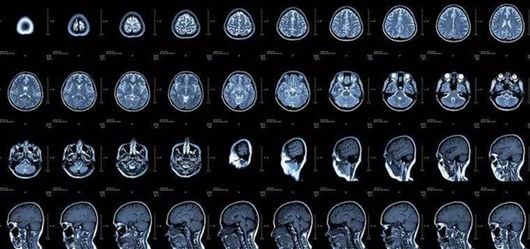

核磁共振—— 把东西“摇摇”再看

核磁共振(MRI)的显影原理是探测水分子的变化。身体里的水分子,在不同组织中含量差别较大,但是每个水分子的磁场磁力线方向都是随意的。

(核磁共振片子长这样哦)

核磁共振机使用较强大的磁场,使人体中所有水分子磁场的磁力线方向一致,这时磁共振机的磁场突然消失,身体中水分子的磁力线方向,突然恢复到原来随意排列的状态。反复多次施加磁场又突然消失,核磁共振机会得到充分的数据并运算后成像。

简单说,就相当于用手摇一摇,让水分子振动起来,再平静下来,感受一下里面的振动。所以,核磁共振也被戏称是“摇摇看”的检查。